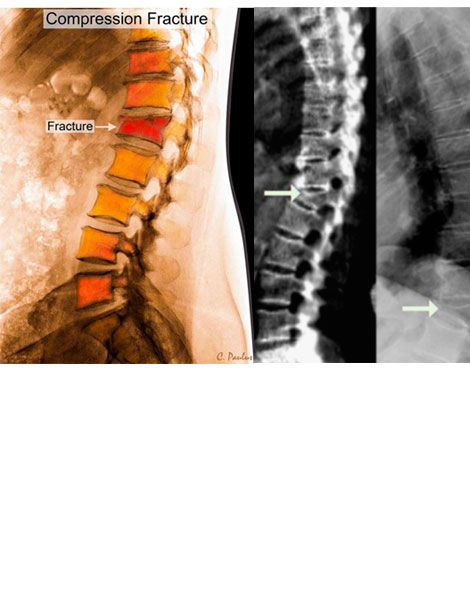

Las fracturas de los huesos que afectan a la columna vertebral se llaman fracturas vertebrales o fracturas vertebrales por compresión

Un examen físico completo, junto con una radiografía y/o una resonancia magnética (RMN) pueden ayudar a su médico a diferenciar entre el dolor causado por una fractura vertebral y el dolor provocado por otros trastornos.

RADIOGRAFIAS: pueden no mostrar fracturas de los cuerpos vertebrales sobre todo en su fase inicial.